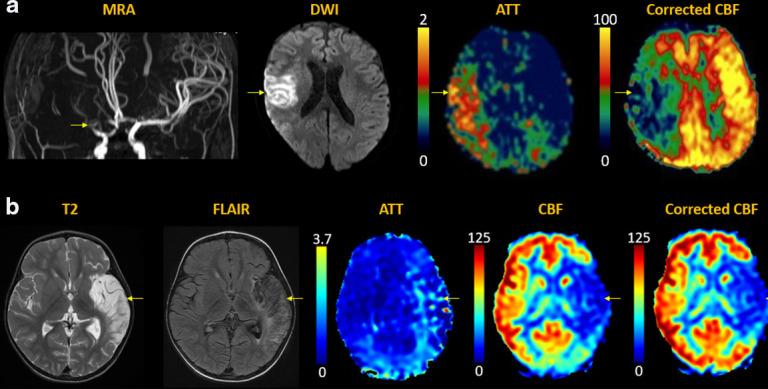

Arterial spin labeling (ASL) is a powerful noncontrast MRI technique for evaluation of cerebral blood flow (CBF). A key parameter in single-delay ASL is the choice of postlabel delay (PLD), which refers to the timing between the labeling of arterial free water and measurement of flow into the brain. Multidelay ASL (MDASL) utilizes several PLDs to improve the accuracy of CBF calculations using arterial transit time (ATT) correction. This approach is particularly helpful in situations where ATT is unknown, including young subjects and slow-flow conditions. In this article, we discuss the technical considerations for MDASL, including labeling techniques, quantitative metrics, and technical artefacts. We then provide a practical summary of key clinical applications with real-life imaging examples in the pediatric brain, including stroke, vasculopathy, hypoxic-ischemic injury, epilepsy, migraine, tumor, infection, and metabolic disease.

动脉自旋标记 (ASL) 是一种强大的非对比 MRI 技术,用于评估脑血流 (CBF)。单延迟 ASL 的一个关键参数是后标记延迟 (PLD) 的选择,它是指动脉游离水标记与脑内血流测量之间的时间间隔。多延迟 ASL (MDASL) 使用多个 PLD 利用动脉通过时间 (ATT) 校正来提高 CBF 计算的准确性。这种方法在 ATT 未知的情况下特别有帮助,包括年轻受试者和低流速情况。本文讨论了 MDASL 的技术注意事项,包括标记技术、定量指标和技术伪影。然后,我们提供了一个实用的总结,介绍了儿科大脑中的关键临床应用,包括中风、血管病变、缺氧缺血性损伤、癫痫、偏头痛、肿瘤、感染和代谢性疾病,并提供了真实的成像示例。